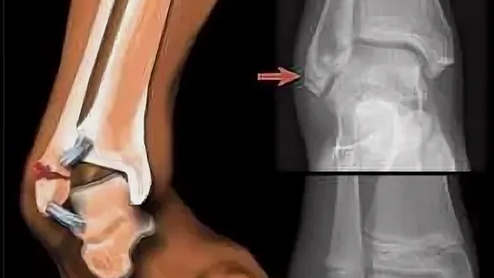

Реконструкция медиальной лодыжки свободным аутотрансплантатом из гребня подвздошной кости после травматического дефекта: клинический случай

Введение Открытые переломы медиальной лодыжки, сопровождающиеся невозможностью ее остеосинтеза вследствие утери костного фрагмента либо его массивной фрагментации, довольно редки в клинической практике. Медиальная лодыжка необходима для обеспечения стабильности голеностопного сустава, и ее реконструкция важна для возможности восстановления функциональных результатов. В мировой литературе описано несколько методик реконструкции, которые можно разделить на две группы: 1) реконструкция свободными...